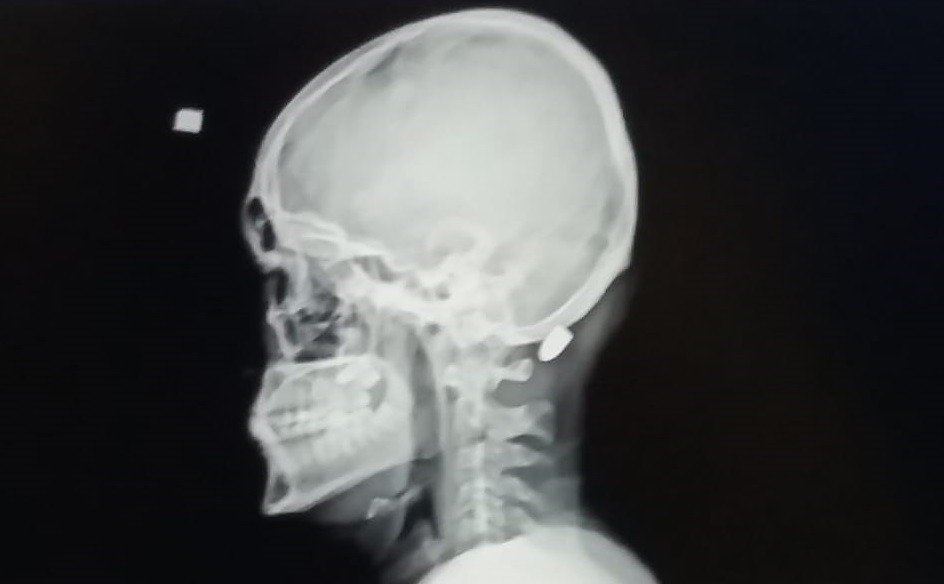

Kentte yetkililerin tüm uyarılarına rağmen yorgun mermi vakalarının arkası kesilmiyor. Yorgun mermi vakalarında kimileri hayatını kaybediyor, kimileri yaralanıyor, kimileri de sakat kalma tehlikesi ile karşı karşıya kalıyor. Trabzon'un Ortahisar ilçesinde 9 Nisan 2016 tarihinde Mustafa Mandıralı (22) isimli inşaat işçisi işe giderken otobüs durağı yakınında nereden ve kim tarafından atıldığı belli olmayan ve "Yorgun mermi" diye tabir edilen merminin hedefi oldu. Merminin başına isabet etmesi sonucu Mandıralı ağır yaralandı.